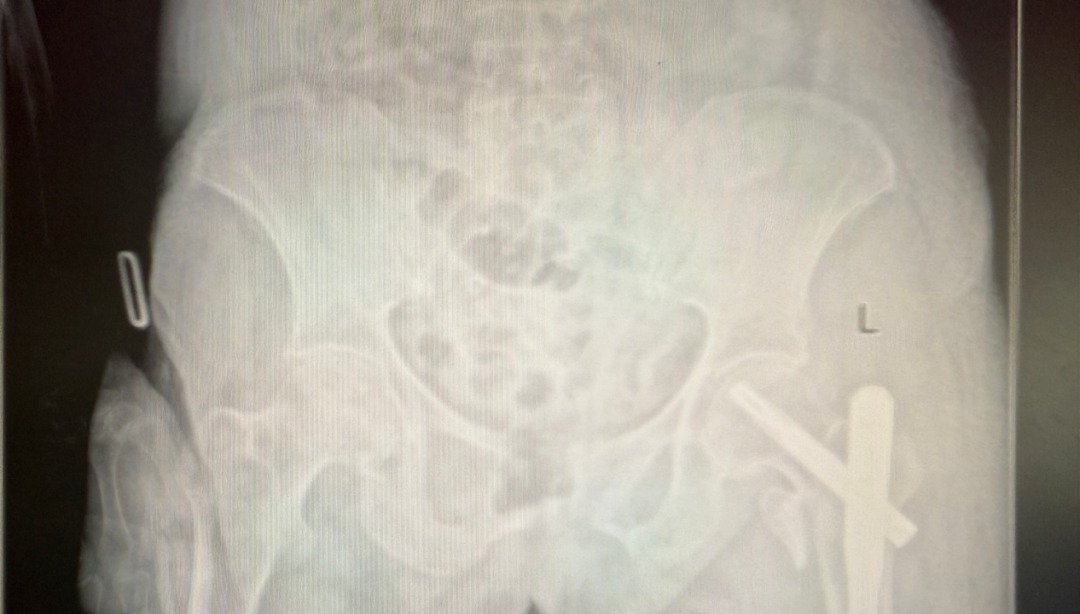

手术当日,杨自权主任团队借助丰富的手术经验,术前在牵引床、G臂辅助下迅速给予患者闭合复位骨折断端,结合经典的“2-1-1”微创手术切口实施手术,手术过程顺利,G臂透视可见骨折复位满意,髓内钉位置满意。术后患者顺利出院,安返家中。